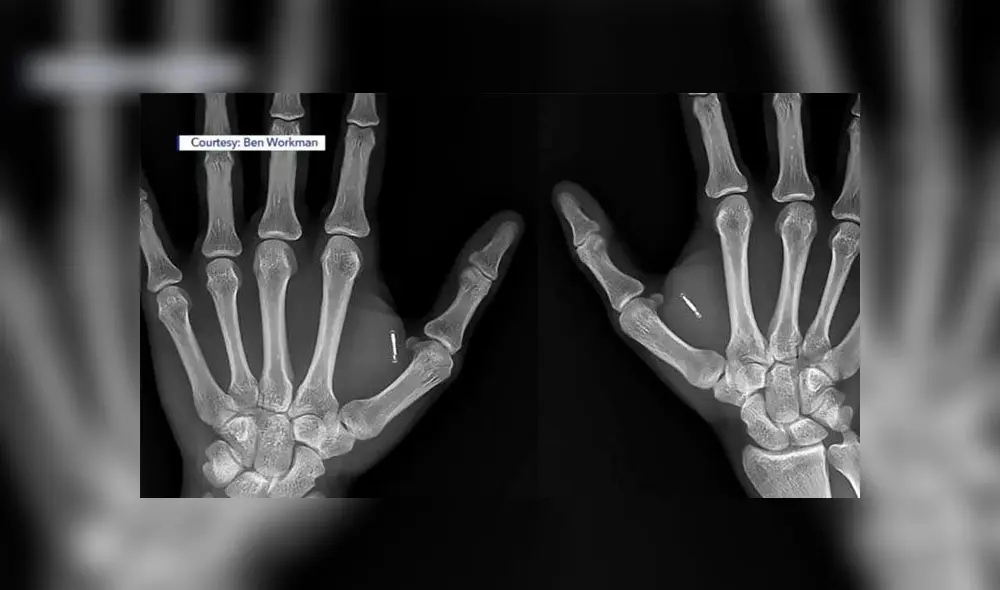

Ben Workman, de 29 años, ha fusionado la tecnología con su propio cuerpo, algo que evoca a Tony Stark, el personaje de la saga Avengers. Tiene implantados en sus manos chips de computadora RFID y NFC, un imán en su mano izquierda y una llave Tesla en la derecha, la cuál usa para abrir su Modelo 3.

El hombre domina uno de los mayores inventos de Elon Musk tras inyectarse chips en sus manos. Foto: Ben Workman

Para conseguir que la llave encaje dentro de su mano, se requirió que un bisturí realizara una incisión de 5 mm en el dorso de la mano hasta los nudillos. Si bien la incisión tardó en sanar, Workman destaca que no ha tenido infecciones ni complicaciones médicas por el implante.